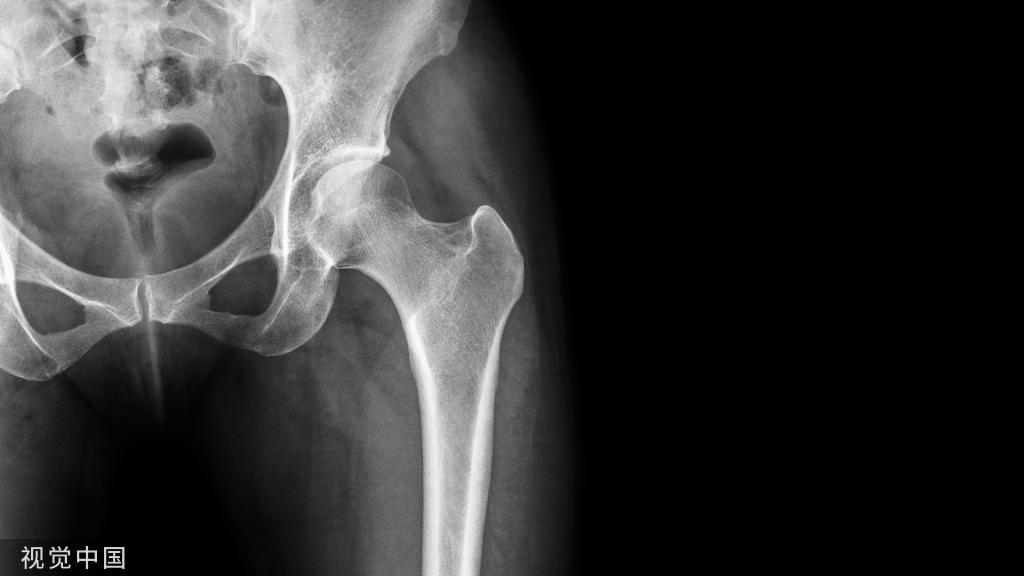

附病例(X线+CT)

病人女性,外伤后骶尾部疼痛,dr片示骶尾关节对应关系差,骶5椎体欠规则。ct重建示骶5椎体粉碎性骨折!

X线